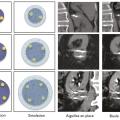

Cryothérapie sous anesthésie locale des tumeurs rénales

Publié le 20 Janvier 2018 || La Revue du Praticien || 68(1):45-7

L’incidence du cancer du rein localisé et de petite taille est en permanente augmentation depuis plusieurs décennies. Cela s’explique en partie par l’essor de l’imagerie médicale puisque plus des deux tiers des cancers du rein sont découverts fortuitement au cours d’un examen d’ima- gerie réalisé pour une autre raison.1, 2 Le…